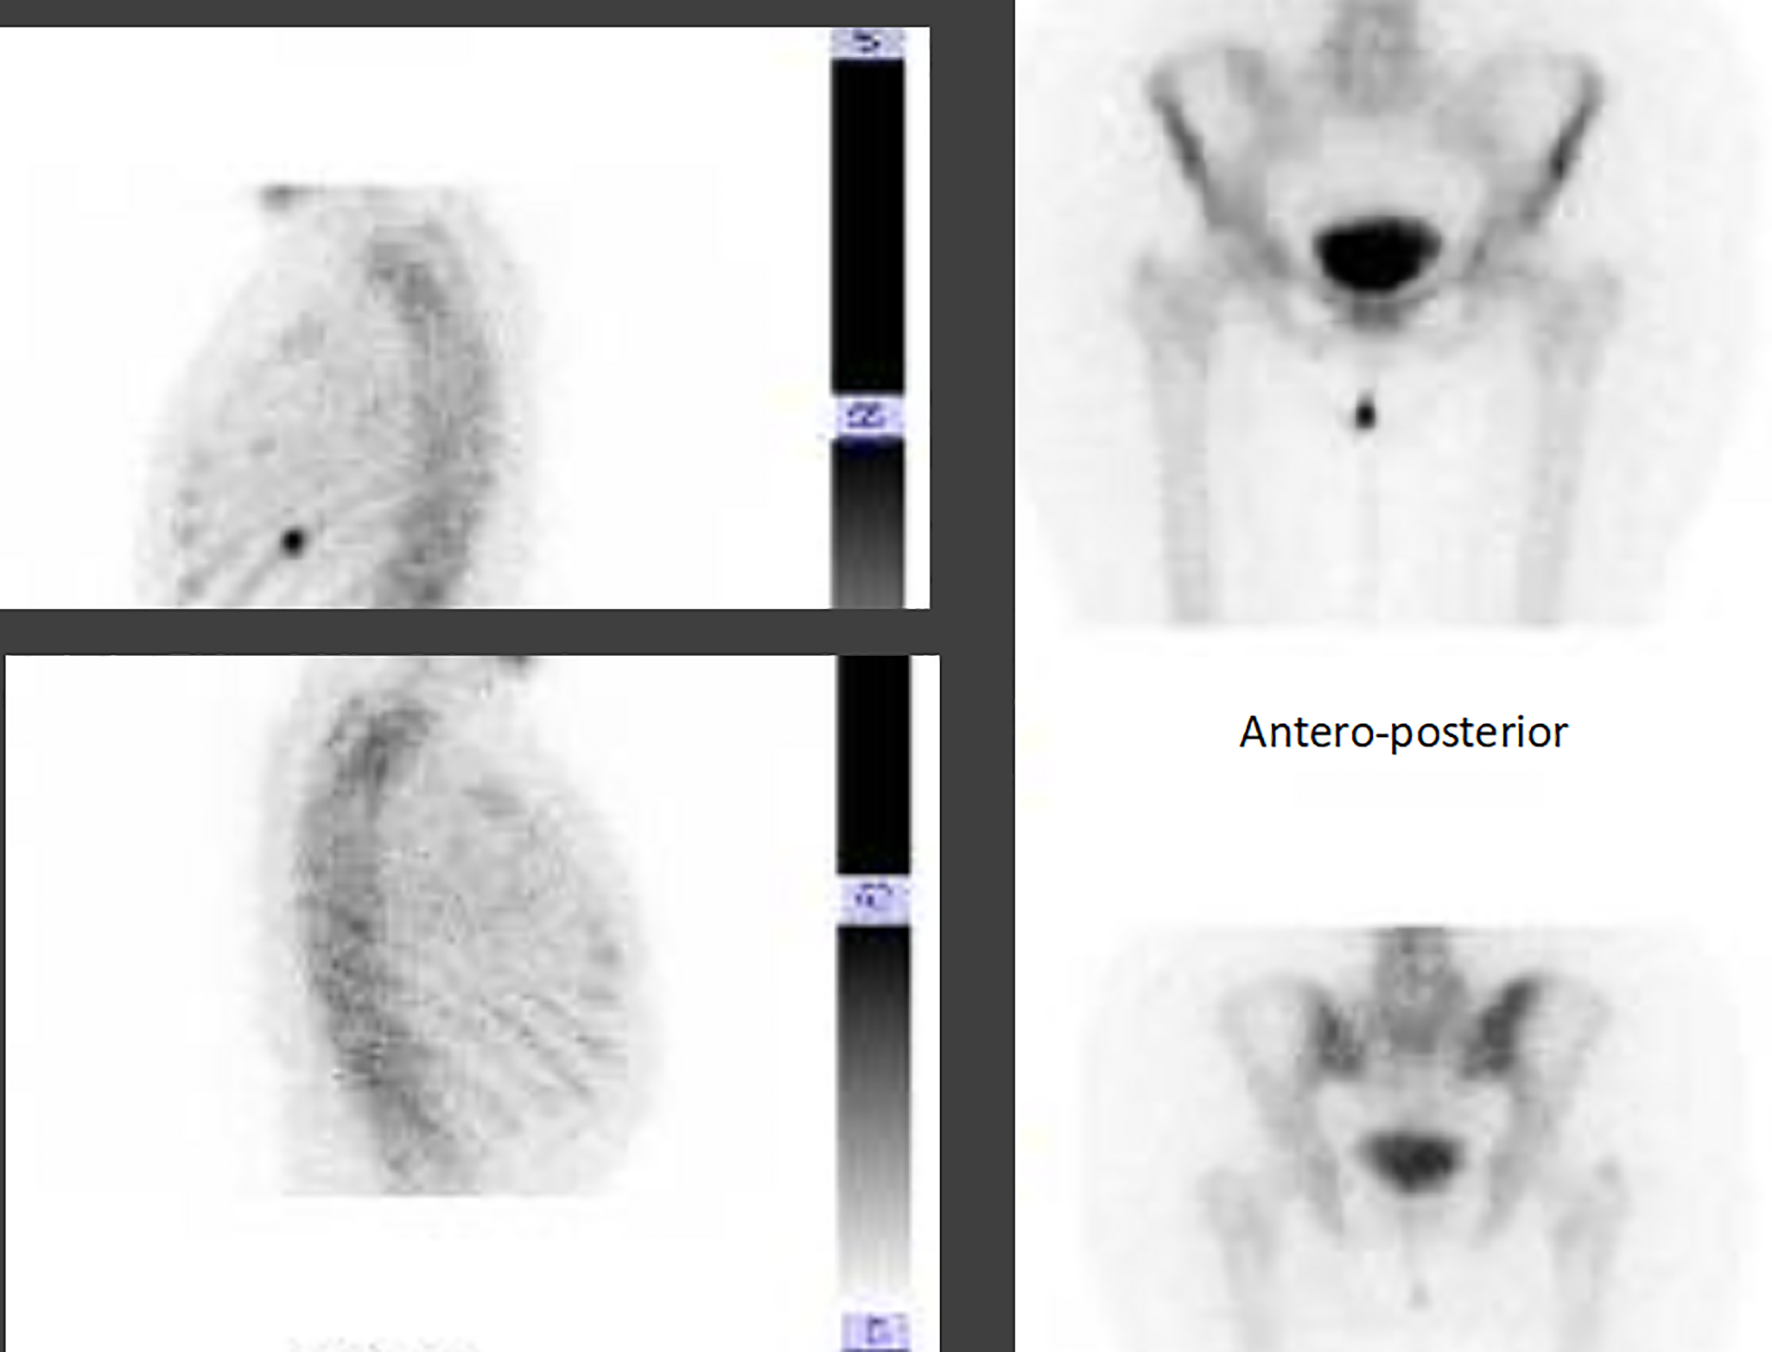

In July 2019, a CT scan demonstrated the presence of multifocal vascularized areas in the right breast cancer with several lymphadenopathies in the ipsilateral axilla and bone rearrangement with cortical interruption at the level of the right iliac wing and at the level of the 10th left rib, highly suggestive for secondary lesions.

Thus, a bone CT scan was done, and the bone involvement was confirmed.

According to the advanced disease stage, in August 2019 she started first-line treatment with ribociclib plus letrozole with the adjunct of a bisphosphonate to prevent skeletal events. However, due to bone pain being non-responsive to painful drugs, in September 2019, the patient also underwent a palliative stereotactic radiotherapy of the left iliac wing and the 10th rib (3,000 cGy on each site), with immediate pain improvement. Overall, the treatment was well tolerated, and only G1 nausea, unspecific osteomuscular pain, and G1 hypercholesterolemia were reported. In December 2019, at the first clinico-radiological evaluation partial response of both breast and axilla localizations, even with the persistency of a satellite nodule, as well as a significant reduction in bone lesions at the bone scan, was reported (Figure 5).

Figure 5

Bone scan evaluation, before and after treatment with ribociclib and letrozole.

In May 2020, an 18FDG-PET CT showed a mild pathological expression of glucidic metabolism in correspondence to bone rearrangement areas with mixed characteristics to the level of the right iliac wing (SUV 2.1) and to the level of the 10th left rib (SUV 2.5). After 4 months, a further reduction in the dimension of breast cancer as well as ipsilateral lymphadenopathies, with no more evidence of satellite nodules, was reported at both mammary ultrasound and breast resonance imaging. Moreover, the 18FDG-PET CT was negative for secondary lesions. Subsequently, in December 2020 the local breast unit choice was surgery of primary tumor and maintenance of systemic endocrine treatment which is still ongoing with good tolerability.